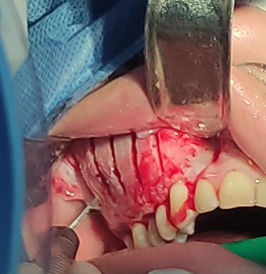

Luego de esperar el periodo de latencia del anestésico (3min), se colocó el campo abierto sobre el área de trabajo para proceder con la siguiente fase, una vez confirmada la anestesia en la zona se procede a la incisión con hoja de bisturí n°15 colocada en un mango n°3, se realizó un colgajo sulcular desde la UD 17 hasta la cara mesial de la UD 13 donde se realizó la descarga en dirección al fondo del surco, luego se realizó levantamiento del colgajo de espesor total con el periostótomo Molt #9. Esto se muestra en la figura 7.

Figura 7. Levantamiento de colgajo mucoperióstico con Molt #9 usando separadores de Branemarck y Minnesota.

Fuente: Historia Clínica Postgrado Cirugía bucal ULAC-IDOLA Julio 2021